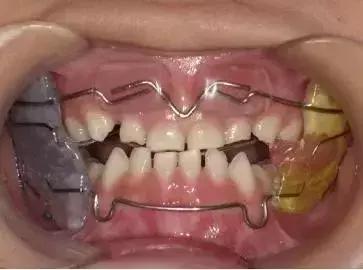

06、功能调节器(简称FR-Ⅲ)

看起来是有点不美观哈,但总比一直“地包天”不美观好撒!